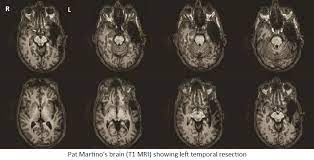

Such sad news. Thanks for sharing. Was fortunate to see him with Joey D on the Live at Yoshi's tour. Such an amazing life story for him to be able to re-achieve virtuoso status after a large chunk of his brain was removed. This image shows just how much was taken away.

He'll inspire generations to come with what he's left behind. In music but also medicine. He's been a unique case study in research of brain and neuroscience. This is extremely interesting article that talks about his injury from a medical stand point but it's filled with stories and anecdotes prior and post recovery.